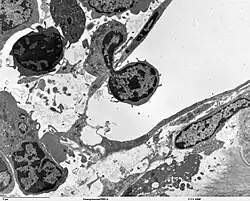

Zellen sind so klein, dass man Eigenschaften ihrer Oberfläche nur mit Hilfe des Elektronenmikroskops (Rasterelektronenmikroskop) erkennen kann. Auf der linken Seite sind weiße Blutzellen sichtbar, die man vor allem an der „gekräuselten“ Oberfläche erkennt. Die roten Blutzellen, die Erythrozyten, sind an ihrer glatten Oberfläche und an den konkav/konvexen Formen erkennbar (kleine Körper mit unterschiedlichen Formen sind die Thrombozyten.). Im unteren Bild auf der linken Seite sieht man, wie sich ein Leukozyt durch ein Blutgefäß-Endothel quält, der vorher adhärent geworden ist. Auf der rechten Seite sieht man verschiedene Ansichten auf das Lungenepithel, vom Lumen aus (oben) und quer zur Membran (unten). Je nach Typ sind die Zellen mit langen Villi, mit kurzen oder nicht mit Villi ausgestattet. Unterschiedliche Elektronendichte und Granularität im unteren Bild deuten die verschiedenen Funktionen der Epithelzell-Typen, was man der Zelle von der Oberfläche her nicht ansehen kann.